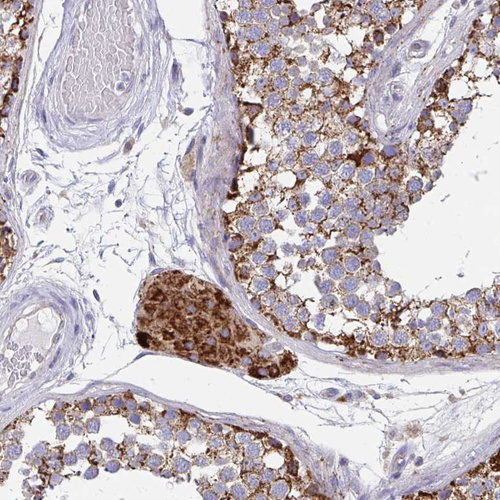

Immunohistochemistry analysis in human liver and lymph node tissues using HPA043922 antibody. Corresponding PC RNA-seq data are presented for the same tissues.